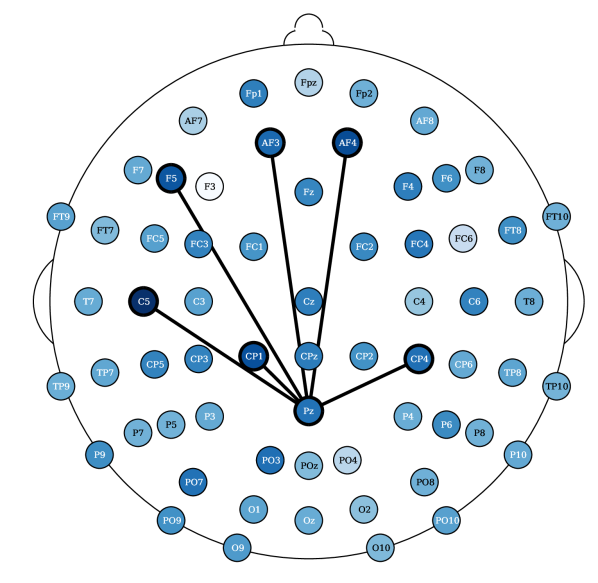

Most relevant electrode relations. Consider the relevance of the attention scores, computed from models (ii) and (iv), both having topographical attention at the EEG channel dimension, and model (iv) with projected random Fourier features in the latent space. These relevances were propagated, using the LRP algorithm [36] described in Appendix 0.E, through the attention style based posterior. Figure 5 shows the relevances plotted in a white to blue scale, from less relevant to most relevant, respectively. The latter only shows the edges that are above the percentile. The presence of an edge between electrodes suggests that either this connection yields a Markovian property for the EEG instance or, otherwise, it is relevant to add fMRI style conditioned on these connections (recall from Section 3.2 that posterior conditions the latent EEG representation such that ). For resting state fMRI, both Figures 10(a) and 5(a) show connections of parietal and occipital channels (O2 electrode in Figure 10(a) and Pz electrode in Figure 5(a)) with frontal and central channels to be the most relevant (above the 99.7 percentile of relevance). Figure 10(a) reports an additional connection between the Oz and PO9 electrodes, a correspondence between an occipital and a parietal-occipital electrode, which is in accordance with connectivity observations reported by Rojas et al. [6]. There were no reported relevances for the electrodes (T) placed in the temporal regions for resting state settings. In contrast, in task-based fMRI synthesis, relevant relationships between temporal (FT9 and TP9) and frontal/central (Fp2 and C1/C2, respectively) electrodes were reported, see Figures 10(b) and 5(b). In both of these figures, connections between central and parietal electrodes were observed. Particularly, there were reported connections between Cz with Pz and CP5 and CP2 electrodes in Figure 10(b). And connections between Pz and P8 with CPz electrodes in Figure 5(b).

Laboratory setup impacts EEG to fMRI synthesis. The results show that it is more difficult, according to the RMSE metric, to synthesize task-based fMRI than resting state. This observation is in contrast with studies that report that resting state fMRI is inherently more complex than task based fMRI [37]. The SSIM metric, in contrast to the RMSE, shows less significant differences for the Oddball recordings in favor of fMRI synthesis in the resting state. However, the CN-EPFL dataset is not in accordance with the latter. This performance heterogeneity across the datasets may not only rise from the characteristics of the recording sessions, but may also be also propelled by the different preprocessing techniques employed. Each dataset is publicly available and is supported with published studies, having unique equipment, experimental protocols, and algorithms. CN-EPFL dataset is the most complete one, with a total of 20 individuals and with a resolution of mm, which makes a total of voxels. These differences, caused by working with 3 Tesla (CN-EPFL dataset) versus 1.5 Tesla (NODDI and Oddball datasets) scanners, significantly impact the spatial resolution, which for the datasets NODDI and Oddball produce and voxels, respectively, with around mm voxel size. One has to further account for the original recording artifacts and disruptions caused by the applied preprocessing techniques. For instance, Oddball dataset contains intra and inter individual wise misalignments across fMRI volumes. This may be the cause of poorer performance of all methods when compared to the other datasets. In addition, Oddball relies on a different EEG electrode positioning system, having a total of electodes that were not placed in accordance with the 10-20 system [26]. Although NODDI and CN-EPFL recordings are in accordance with this system, each selected unique electrode locations (see the different electrode placements between Figures 5(a) and 5(b)). Finally, the different EEG sampling frequencies, with Hz, Hz and Hz considered in NODDI, Oddball and CN-EPFL recordings, respectively, further affect architectural operations and subsequently impact the learning.